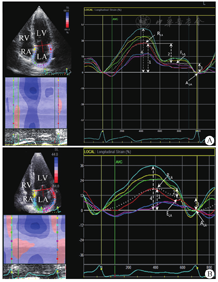

在心尖左心室长轴、心尖左心室二腔和心尖四腔切面上,于收缩末期勾勒出左心室心内膜的轮廓,应用软件计算左心室整体纵向应变值(global longitudinal peak strain,GLS)。在心尖四腔切面对左心房进行应变评估。从绘制的曲线中确定了3个不同的左心房应变段:收缩期峰值应变(RLA)、舒张早期峰值应变(ELA)和舒张晚期峰值应变(ALA)。RLA反映左心房储器功能,左心房管道功能由RLA和ELA之间的差值计算,左心房收缩功能由ELA和ALA之间的差值计算[6],见图2。

RV:右心室;LV:左心室;LA:左心房;RA:右心房;;AVC:主动脉瓣关闭;RLA:收缩期峰值应变;ELA:舒张早期峰值应变;ALA:舒张晚期峰值应变。黄色曲线表示间隔基底段的应变,红色曲线表示侧基底段的应变,全部节段应变的平均值用白色点状曲线表示。LA峰值应变为心尖四腔切面中任何节段的最高应变(4);RLA反映LA储器功能(1);LA管道功能(2)由RLA和ELA之间的差值计算;LA收缩功能(3)由ELA和ALA之间的差值计算。与健康人(A)相比,Ⅰ级DD糖尿病患者(B)的LA管道功能明显降低